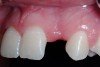

A 19-year-old non-smoking female presented for tooth replacement at the maxillary right and left lateral incisors, which were congenitally missing (Figure 1). The post-orthodontic result was adequate for the placement of 3-mm one-piece small-diameter implants. The preoperative radiographs can be seen in Figure 2 and Figure 3. The pretreatment clinical view in Figure 4 and Figure 5 shows the small intertooth space present in the lateral incisor areas. One of the most challenging tasks with congenitally missing lateral incisor cases is to create an acceptable soft tissue emergence profile from a crestal profile that is flat from the mesial of the canines to the distal of the centrals (Figure 4 and Figure 5). After pretreatment planning which consisted of a complete medical and dental history, radiographic analysis, and upper and lower study models mounted by a facebow transfer technique, the fabrication of a TempStent II surgical guide was completed. Figure 6 and Figure 7 show the occlusal view of the TempStent II guide on the study cast and in the oral cavity, respectively.